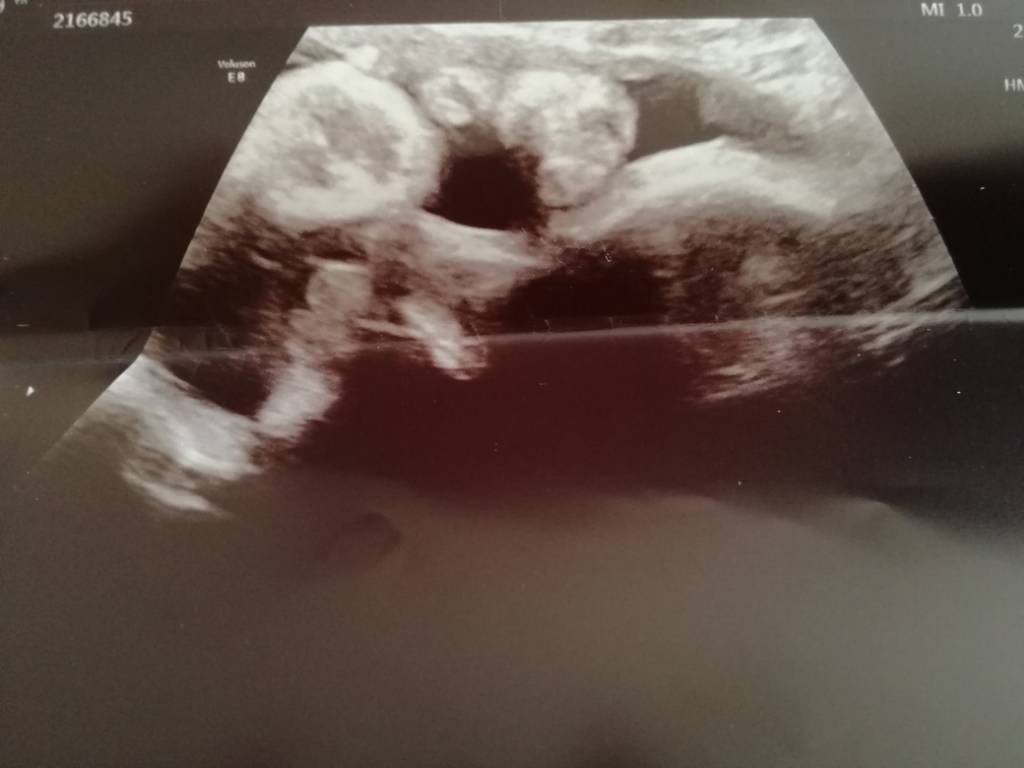

A to maluszek. Dotyka rączkami buzi [emoji4]Zobacz załącznik 873126